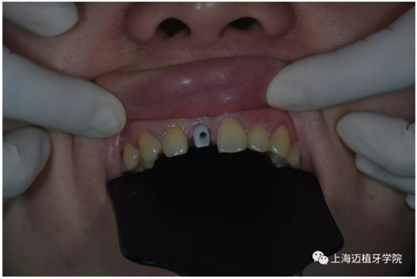

戴牙前口內(nèi)照片:

去除愈合基臺:

口內(nèi)個性化基臺: